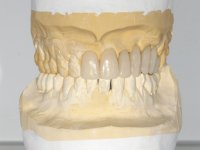

A temporary acrylic bridge made in the laboratory with 7 elements was made, with teeth 11,21, 25 and 26 as pillars. The old bridge was removed and tooth 24 was extracted. The provisional bridge after relining was cemented in the mouth. Two implants were placed in the teeth 22 and 24 and 3 months after this intervention an impression was made to make a temporary bridge screwed over the implants and cemented to the teeth. The bridge was placed in the mouth and teeth 25 and 26 were extracted. 3 months later, surgery was performed to fill the maxillary sinus and 6 months later the implant was placed in the location of tooth 26. After osseointegration of this implant, the final impression was made for the final work. The bridge over the implants was permanently screwed on and the bridge over the teeth was cemented with resin-reinforced glass ionomer cement.